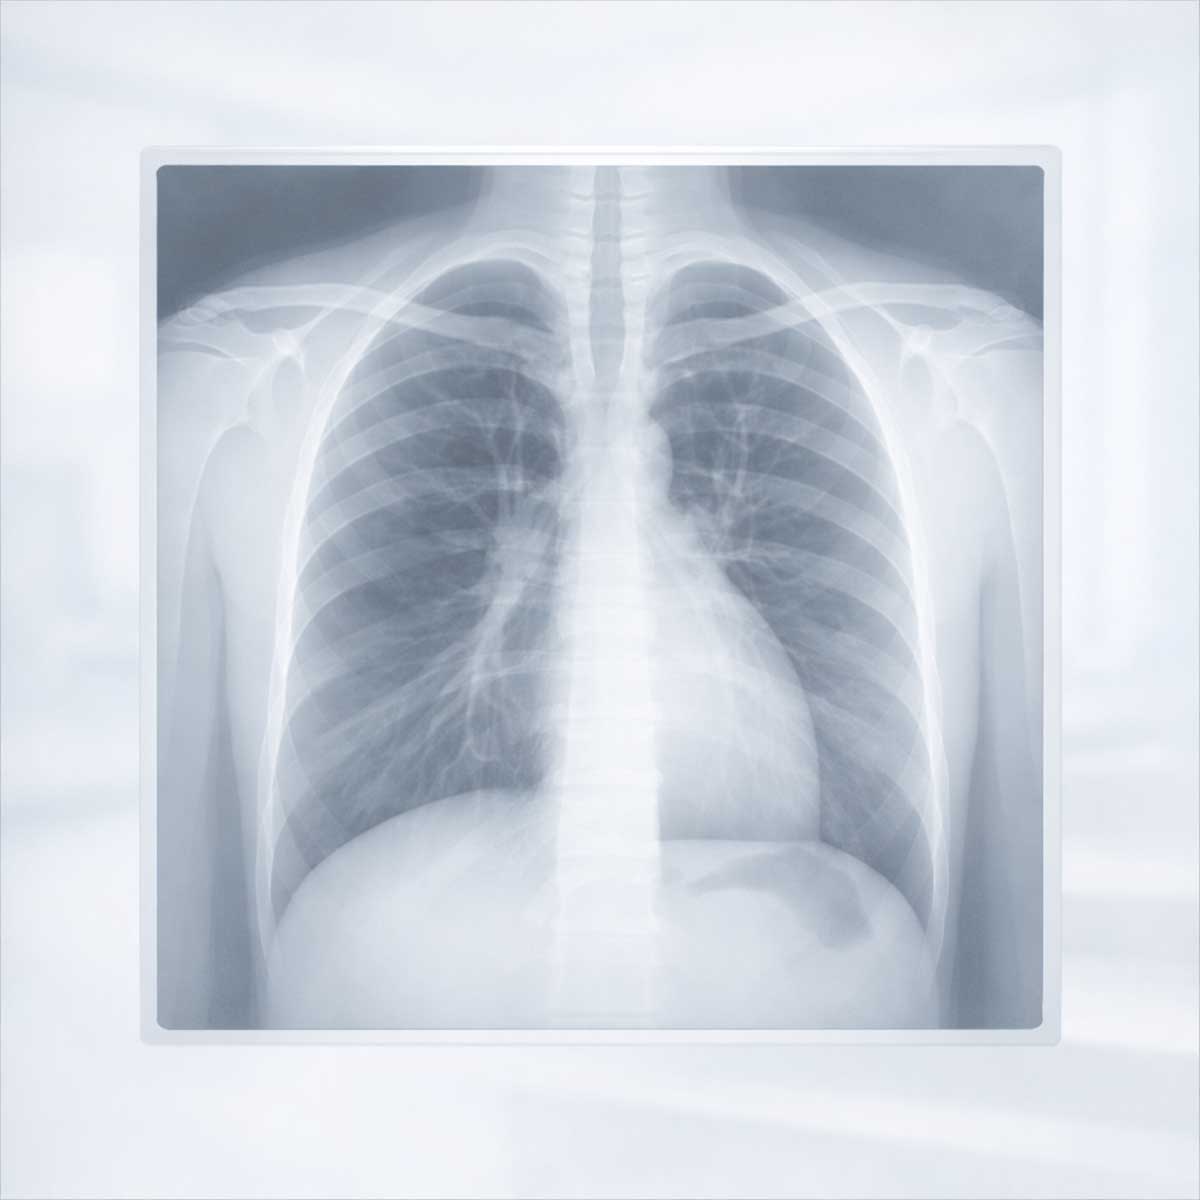

Рентген легких — один из наиболее распространенных и доступных методов диагностики заболеваний дыхательной системы. Исследование позволяет получить обзорное изображение органов грудной клетки и часто используется как первый этап оценки состояния легких при появлении симптомов.

Рентгенография — это метод лучевой диагностики, при котором изображение внутренних органов формируется с помощью рентгеновского излучения. Лучи проходят через ткани организма и по-разному задерживаются в зависимости от их плотности, что позволяет получить контрастное изображение на снимке.

В результате врач видит обзорную картину органов грудной клетки, включая легочные поля, корни легких и окружающие структуры. Рентгеновский снимок является плоским, то есть отражает суммарное изображение тканей, расположенных на пути прохождения лучей.

На рентгеновском снимке врач оценивает:

Рентген позволяет не только обнаружить изменения в легких, но и определить, в какой дольке легкого эти изменения расположены. О дольках легких подробно написано в отдельной статье.

Рентген позволяет выявить выраженные изменения, однако не всегда дает возможность точно определить их характер.

В таблице ниже перечислены основные структуры и элементы, которые врач оценивает при анализе рентгеновского снимка легких. Это помогает понять, какую информацию можно получить в ходе исследования и почему результаты рентгена требуют профессиональной интерпретации.

| Что оценивается | Что позволяет увидеть |

|---|---|

| Легочные поля | Участки затемнения или просветления |

| Контуры | Возможные деформации или смещения |

| Корни легких | Изменения структуры |

Рентген легких является обзорным методом диагностики и имеет свои ограничения. Он может не выявлять мелкие или начальные изменения, особенно если они располагаются глубоко в ткани легкого или перекрываются другими структурами.